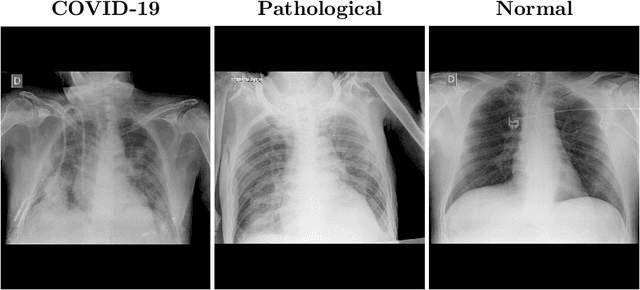

Abstract:In 2020, the SARS-CoV-2 virus causes a global pandemic of the new human coronavirus disease COVID-19. This pathogen primarily infects the respiratory system of the afflicted, usually resulting in pneumonia and in a severe case of acute respiratory distress syndrome. These disease developments result in the formation of different pathological structures in the lungs, similar to those observed in other viral pneumonias that can be detected by the use of chest X-rays. For this reason, the detection and analysis of the pulmonary regions, the main focus of affection of COVID-19, becomes a crucial part of both clinical and automatic diagnosis processes. Due to the overload of the health services, portable X-ray devices are widely used, representing an alternative to fixed devices to reduce the risk of cross-contamination. However, these devices entail different complications as the image quality that, together with the subjectivity of the clinician, make the diagnostic process more difficult. In this work, we developed a novel fully automatic methodology specially designed for the identification of these lung regions in X-ray images of low quality as those from portable devices. To do so, we took advantage of a large dataset from magnetic resonance imaging of a similar pathology and performed two stages of transfer learning to obtain a robust methodology with a low number of images from portable X-ray devices. This way, our methodology obtained a satisfactory accuracy of $0.9761 \pm 0.0100$ for patients with COVID-19, $0.9801 \pm 0.0104$ for normal patients and $0.9769 \pm 0.0111$ for patients with pulmonary diseases with similar characteristics as COVID-19 (such as pneumonia) but not genuine COVID-19.